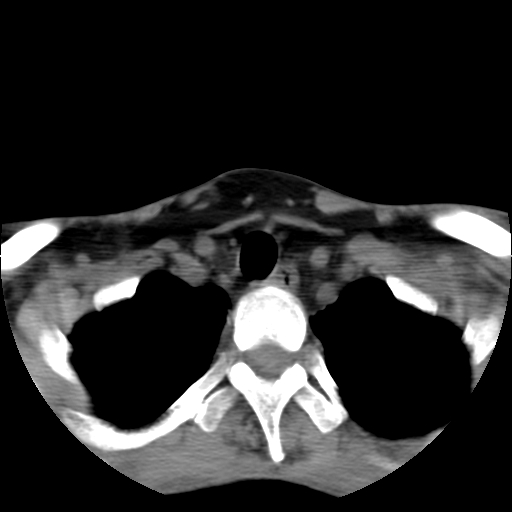

标题: CT24019:男,45岁,发现颈部肿物5个月。 [打印本页]

标题: CT24019:男,45岁,发现颈部肿物5个月。

男,45岁,发现颈部肿物5个月,彩超示:双侧颈部及下颌部软组织增厚。